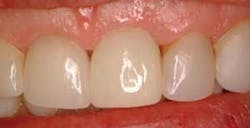

In addition, food now collects in these areas, and when she speaks she finds herself spitting when she talks, which she has never done before. She both loves and hates her new implant. We treated her with a diode laser (Picasso Lite, AMD Lasers) to loosen the gingival attachment and then placed some dermal filler (Juvederm Ultra Plus XC, Allergan Corporation) into the papilla to rebuild it.

Fig. 5 shows the rebuilt gingival papilla that fills up the black triangles and takes care of her esthetic and functional concerns. The treatment appointment was approximately five minutes, and she can expect this to last for eight months or longer, at which point it will need to be done again. This is a very minimally invasive approach to a very difficult situation and it completely satisfied this patient.